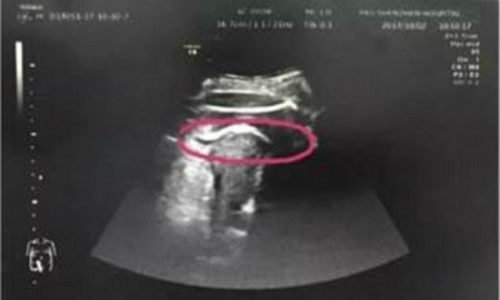

Thai nhi đạp thủng tử cung khiến mẹ suýt tử vong